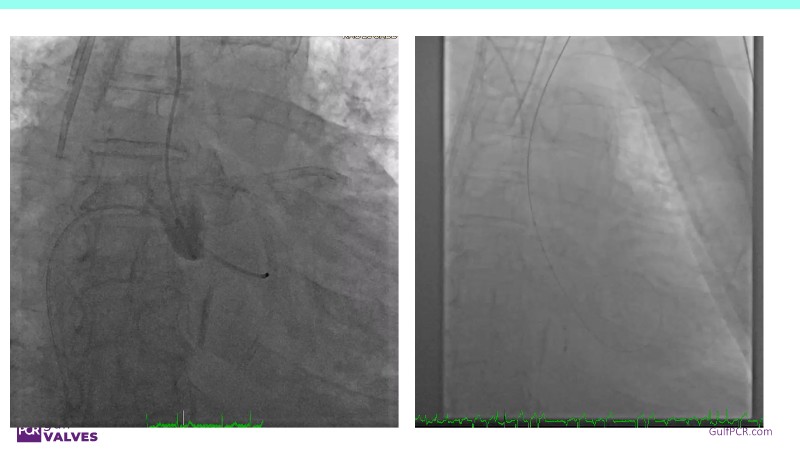

Discover a selection of cases showcasing the key features of the Navitor Valve System and its clinical applications. This session explores auxiliary access, the use of Navitor in alternative access and complex PCI, its performance in challenging peripheral anatomies, and innovative outcomes with the Vantage 30D system.